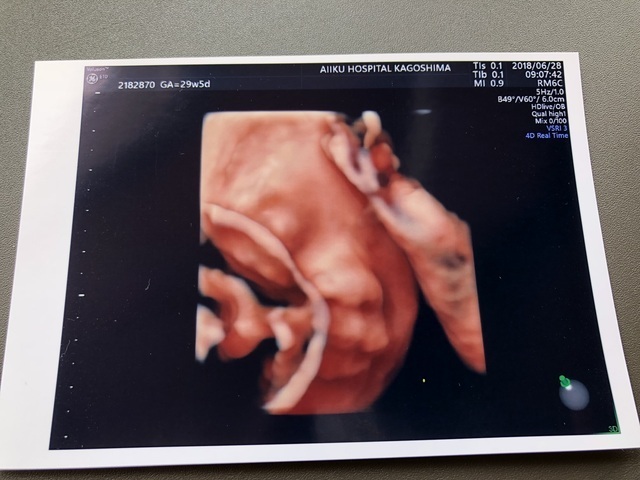

24週0日(24w0d・女の子)|ゆっちゃんちゃん さん(32歳)

エコー写真撮影時のエピソード:

前回の健診では、顔を手で隠していて見せてくれなかったけれど、この健診では顔をはっきり見せてくれてうれしかったです。

またこの次の健診では顔を隠していました。 なかなかはっきり見せてくれるときが少ないです。